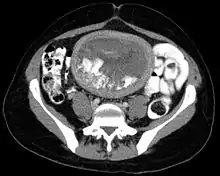

In rare cases a hydatidiform mole co-exists in the uterus with a normal, viable fetus. These cases are due to twinning. The uterus contains the products of two conceptions: one with an abnormal placenta and no viable fetus (the mole), and one with a normal placenta and a viable fetus. Under careful surveillance it is often possible for the woman to give birth to the normal child and to be cured of the mole.[9]